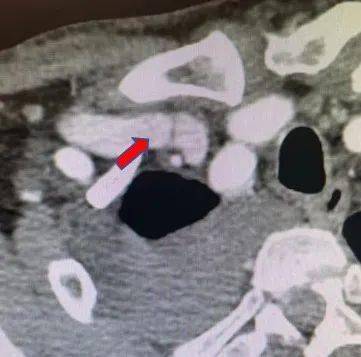

张东亮主任耐心听完患者的叙述 , 给出了诊断:“肿胀手综合征” 。 肿胀手的主要原因是自体动静脉内瘘成型后 , 静脉发生动脉样改变 , 管腔内静水压力升高 , 当静脉血液回流不畅时就会导致压力进一步升高 , 从而形成患侧手臂显著增粗的病症 , 这在起搏器植入的血透患者中 , 发生率更高 。 张主任立刻为老李安排检查:首先是超声明确内瘘吻合口内径 , 发现血管流量尚可 , 静脉弓汇入锁骨下静脉处相对性狭窄伴迂曲 。 随后又进行了上肢及深静脉CT三维重建(CTA+CTV) , 发现主要病变为锁骨下静脉汇入头臂静脉处静脉瓣增生狭窄(如下图)